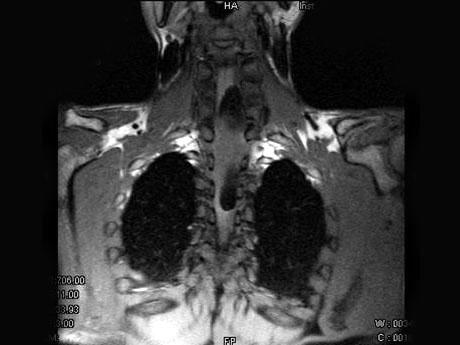

男,37岁,肢体活动不利、酸胀1年余,MRI扫描见椎管内长条形T 和T

和T 高信号,脂肪抑制序列呈低信号,应考虑为()

高信号,脂肪抑制序列呈低信号,应考虑为()

A.椎管内脂肪瘤

B.室管膜瘤

C.椎管内血肿

D.椎管内转移瘤

男,37岁,肢体活动不利、酸胀1年余,MRI扫描见椎管内长条形T1和T2高信号,

[单选题]男,37岁,肢体活动不利、酸胀1年余,MRI扫描见椎管内长条形T1和T2高信号,脂肪抑制序列呈低信号,应考虑为()A . 椎管内脂肪瘤B . 室管膜瘤C . 椎管内血肿D . 椎管内转移瘤E . 未见异常